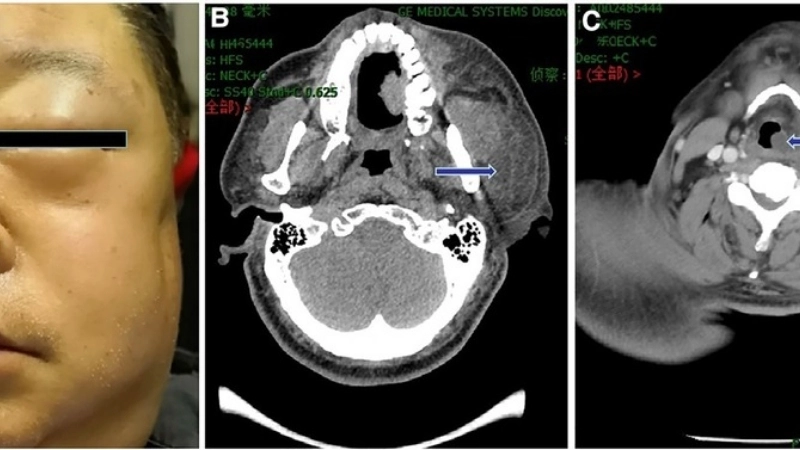

- Triệu chứng bệnh quai bị điển hình nhất là sưng và đau một hoặc cả hai tuyến nước bọt mang tai, khiến một bên hoặc cả hai bên má phình to ra.

Nhận biết qua các hình ảnh bệnh quai bị phổ biến